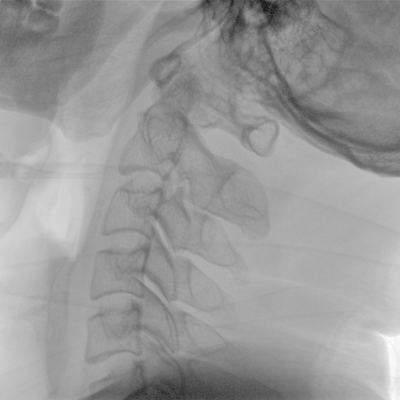

骨科: 經(jīng)皮錐體成形術(shù)、經(jīng)皮椎間盤臭氧治療術(shù)、胸脊椎固定、骨活檢、腰椎內(nèi)固定術(shù)等。

優(yōu)質(zhì)平板探測(cè)器、可靈活升降調(diào)節(jié)SID、獨(dú)特圖像處理系統(tǒng)、高品質(zhì)濾線柵,大視野成像清晰不失真。

采用智能劑量控制技術(shù),可根據(jù)不同體型和不同部位,準(zhǔn)確調(diào)節(jié)投照劑量。使操作者在任何使用環(huán)境下,都能實(shí)現(xiàn)低劑量、診視圖像清晰的效果。